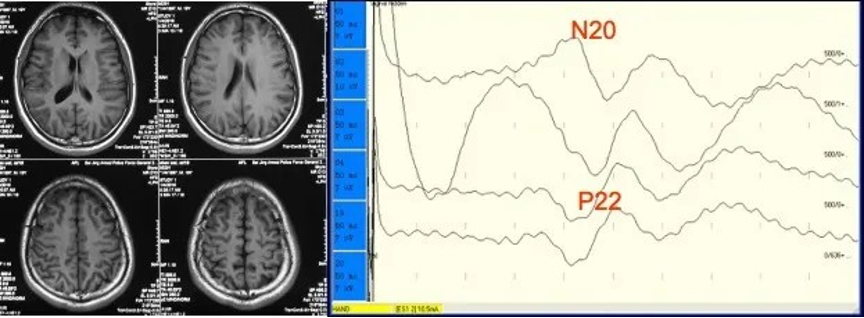

We routinely perform preoperative and post-operative EEG examinations in patients with epilepsy, as well as intraoperative ECOG monitoring. Combining functional area location and subcortical stimulation, we could accurately locate the epileptic focus and the functional area, and ensure accurate removal of the lesion. We carry out monitoring of the abnormal electromyographic response of hemifacial spasm and hearing to effectively ensure the disappearance of post-operative spasms and the preservation of hearing.

Locate the central sulcus by evoked potential